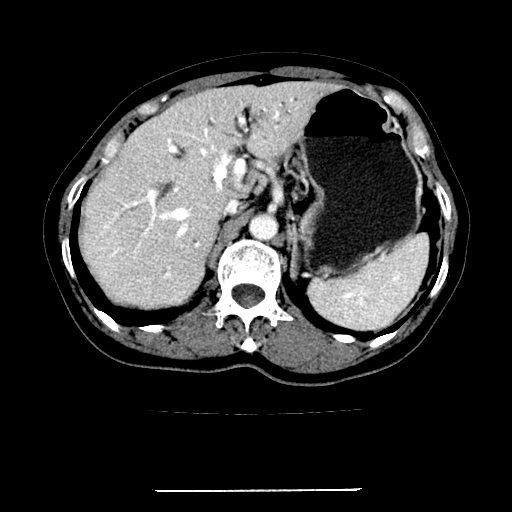

标题: CT22301:女,67岁,上腹部疼痛一周伴皮肤黄染,无发热。 [打印本页]

女,67岁,上腹部疼痛一周伴皮肤黄染,无发热。

左叶肝内胆管结石,并远端肝内胆管扩张。

考虑:肝内胆管结石继发肝内胆管扩张,右肾旋转不良。

肝内外胆管结石并肝内胆管扩张。

肝内外胆管扩张,左叶胆管内结石

1、肝门高密度影下层面和胰头层面可见轻度胆管扩张,而静脉和延迟期均未见扫描完胰头,不能完全排除胰头占位。2、肝门部高密度影,考虑钙化或结石。

考虑肝门胆管癌伴门脉左支受侵包埋,建议mrcp进一步检查。